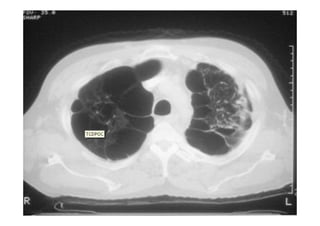

Utiliza-se com frequência p/ avaliar:

Alterações patológicas e diagnóstico de pneumopatias;

Radiografia e TC de tórax

Utiliza-se com frequênciap/ avaliar: O posicionamento do TOT: 4-6 cm acima da carina; Se os pulmões estão sendo aerados adequadamente; Alterações patológicas e diagnóstico de pneumopatias; Outros. Radiografia e TC de tórax